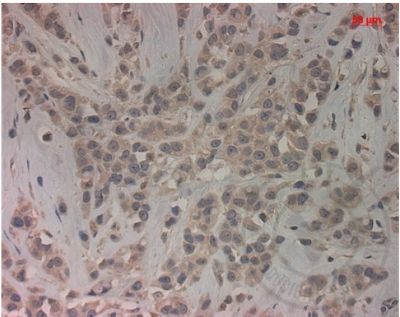

乳腺癌易感基因相关蛋白2免疫组化荧光抗体

中文名称乳腺癌易感基因相关蛋白2

产品应用WB=1:500-2000 ELISA=1:500-1000 IHC-P=1:400-800 IHC-F=1:400-800 Flow-Cyt=1μg/Test IF=1:100-500 (石蜡切片需做抗原修复)

细胞定位细胞核